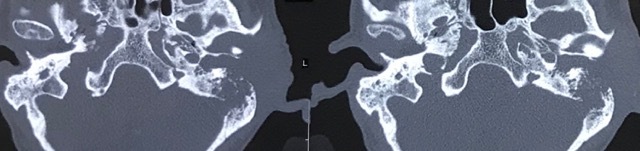

Cholesteatoma Diagrams

Cholesteatoma Clinical

Scans